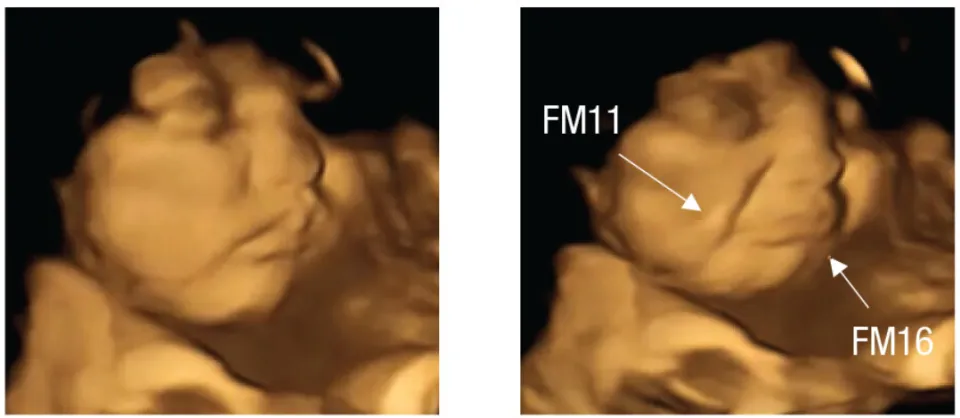

Một nghiên cứu được công bố bởi Đại học Durham cho thấy thói quen kén ăn có thể bắt đầu từ trước khi sinh. Nghiên cứu đã sử dụng công nghệ siêu âm 4D để quan sát phản ứng của thai nhi với các hương vị thực phẩm khác nhau trong bụng mẹ. Theo nghiên cứu, khi các bà mẹ tương lai ăn cà rốt, loại rau củ bổ dưỡng này, trong thai kỳ, chúng dường như kích thích "tiếng cười" hoặc nụ cười ở thai nhi đang phát triển. Tuy nhiên, khi các bà mẹ ăn cải xoăn, một loại rau lá xanh có vị đắng , thì tác dụng ngược lại xảy ra, khiến nụ cười của thai nhi chuyển thành "nét mặt cau có" hoặc "mặt chua chát".

Nghiên cứu ghi nhận bằng chứng trực tiếp đầu tiên cho thấy thai nhi phản ứng khác nhau với các mùi và vị khác nhau, một phát hiện được họ rút ra bằng cách quan sát biểu cảm khuôn mặt của thai nhi. Phân tích hình ảnh siêu âm 4D của 100 phụ nữ mang thai, các nhà nghiên cứu đã quan sát cách thai nhi phản ứng với hương vị thực phẩm mà mẹ chúng ăn.

Các bà mẹ tham gia nghiên cứu, độ tuổi từ 18 đến 40, đã được siêu âm vào tuần thứ 32 và 36 của thai kỳ. Khoảng 20 phút trước khi siêu âm, họ được cho uống một viên nang chứa khoảng 400 mg bột cà rốt hoặc cải xoăn, chất duy nhất họ tiêu thụ trong ít nhất một giờ. Hơn nữa, những người phụ nữ này không ăn hoặc uống bất cứ thứ gì khác có chứa cà rốt hoặc cải xoăn vào ngày hôm đó. Các phản ứng trên khuôn mặt cho thấy ngay cả một lượng nhỏ hương vị cà rốt hoặc cải xoăn cũng đủ để kích thích phản ứng của thai nhi.